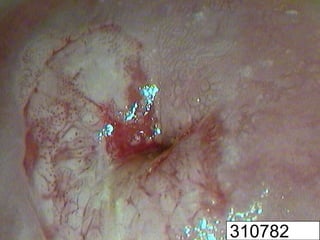

H-SIL and microinvasive

cervical cancers